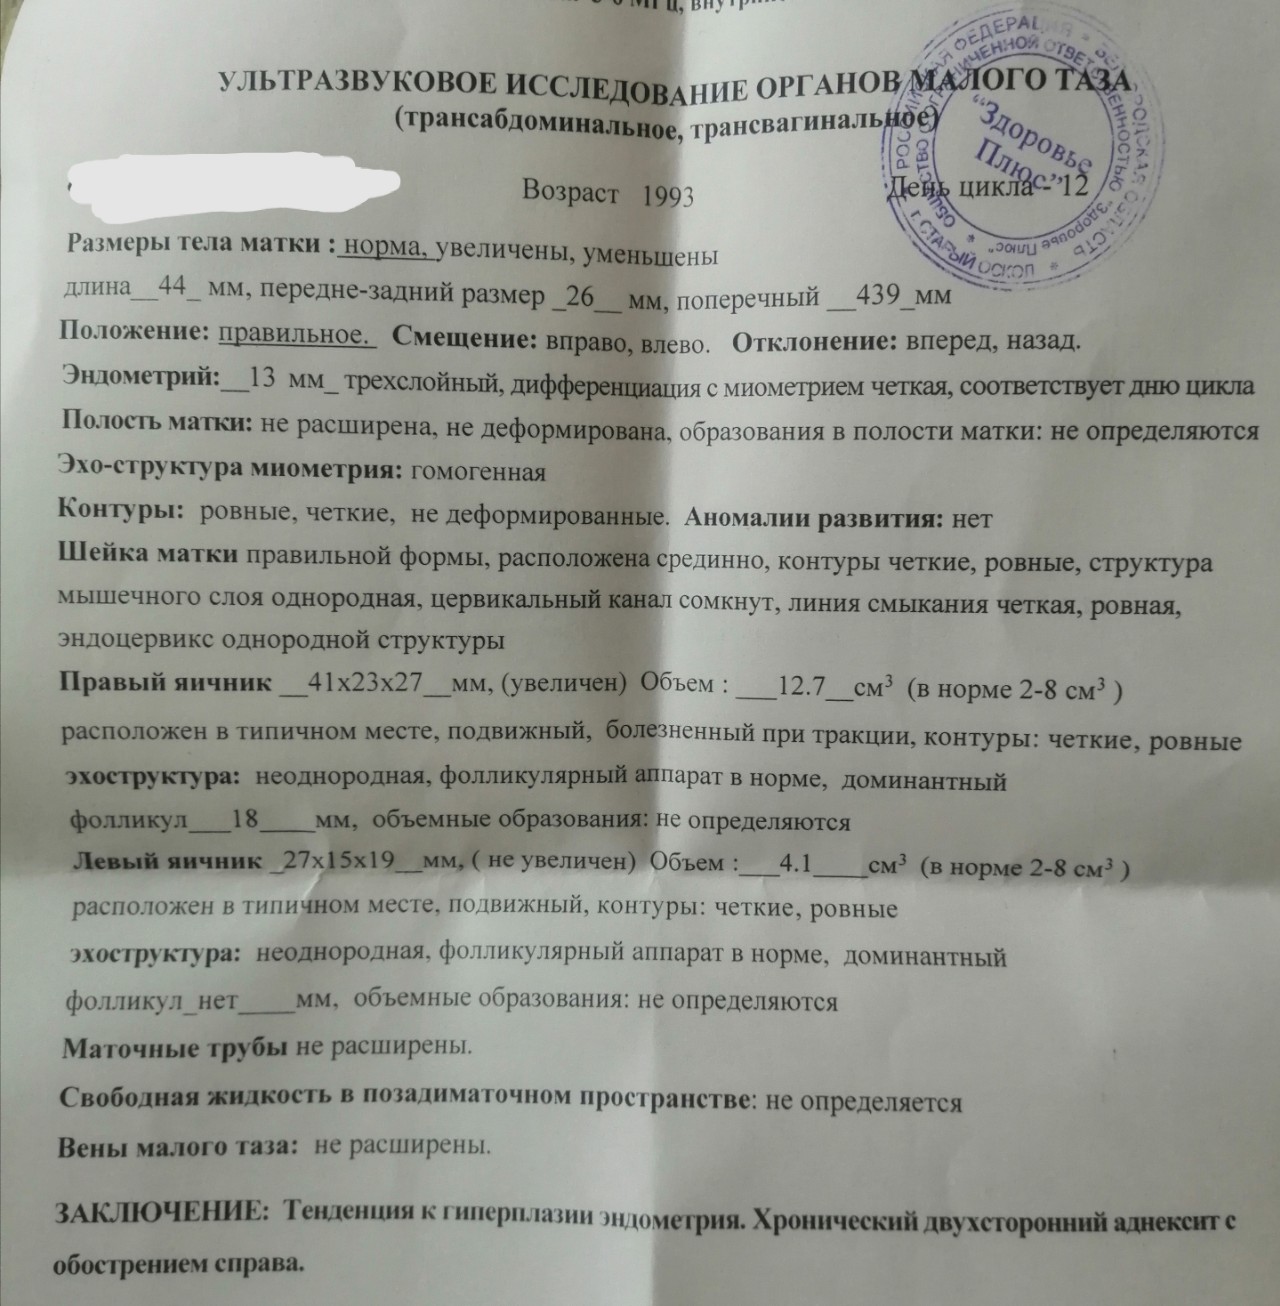

Медицинская диагностика: Гиперплазия эндометрия на УЗИ

Раздел: Мудрость в объективе